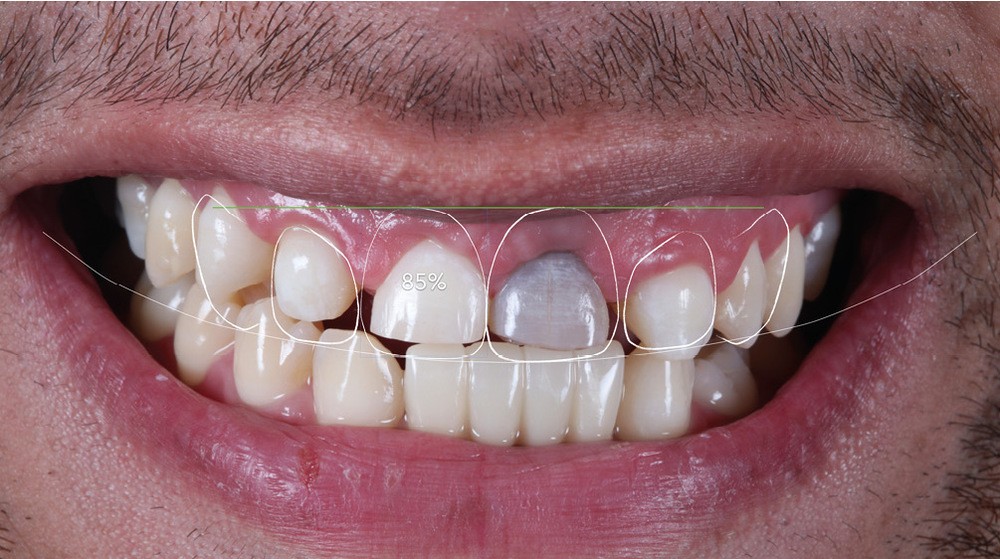

Acte 1 : consultation (fig. 1)

Le patient présente des agénésies génétiques multiples : sur le secteur maxillaire antérieur, il lui manque les deux latérales 12 et 22 ainsi que la canine droite 13 (fig. 1).

Celle du visage d’abord, qui met en évidence un décalage des axes importants : la ligne horizontale maxillaire et la ligne bipupillaire sont loin d’être parallèles. La ligne interincisive part en diagonale, induisant un effet largement inesthétique [2].

L’analyse du sourire du patient révèle une difficulté supplémentaire : haute, la ligne du sourire expose les collets et la gencive, ce qui rend le cas complexe.

Au niveau endobuccal sont observés un défaut des proportions dentaires et une dyschromie importante sur 21.